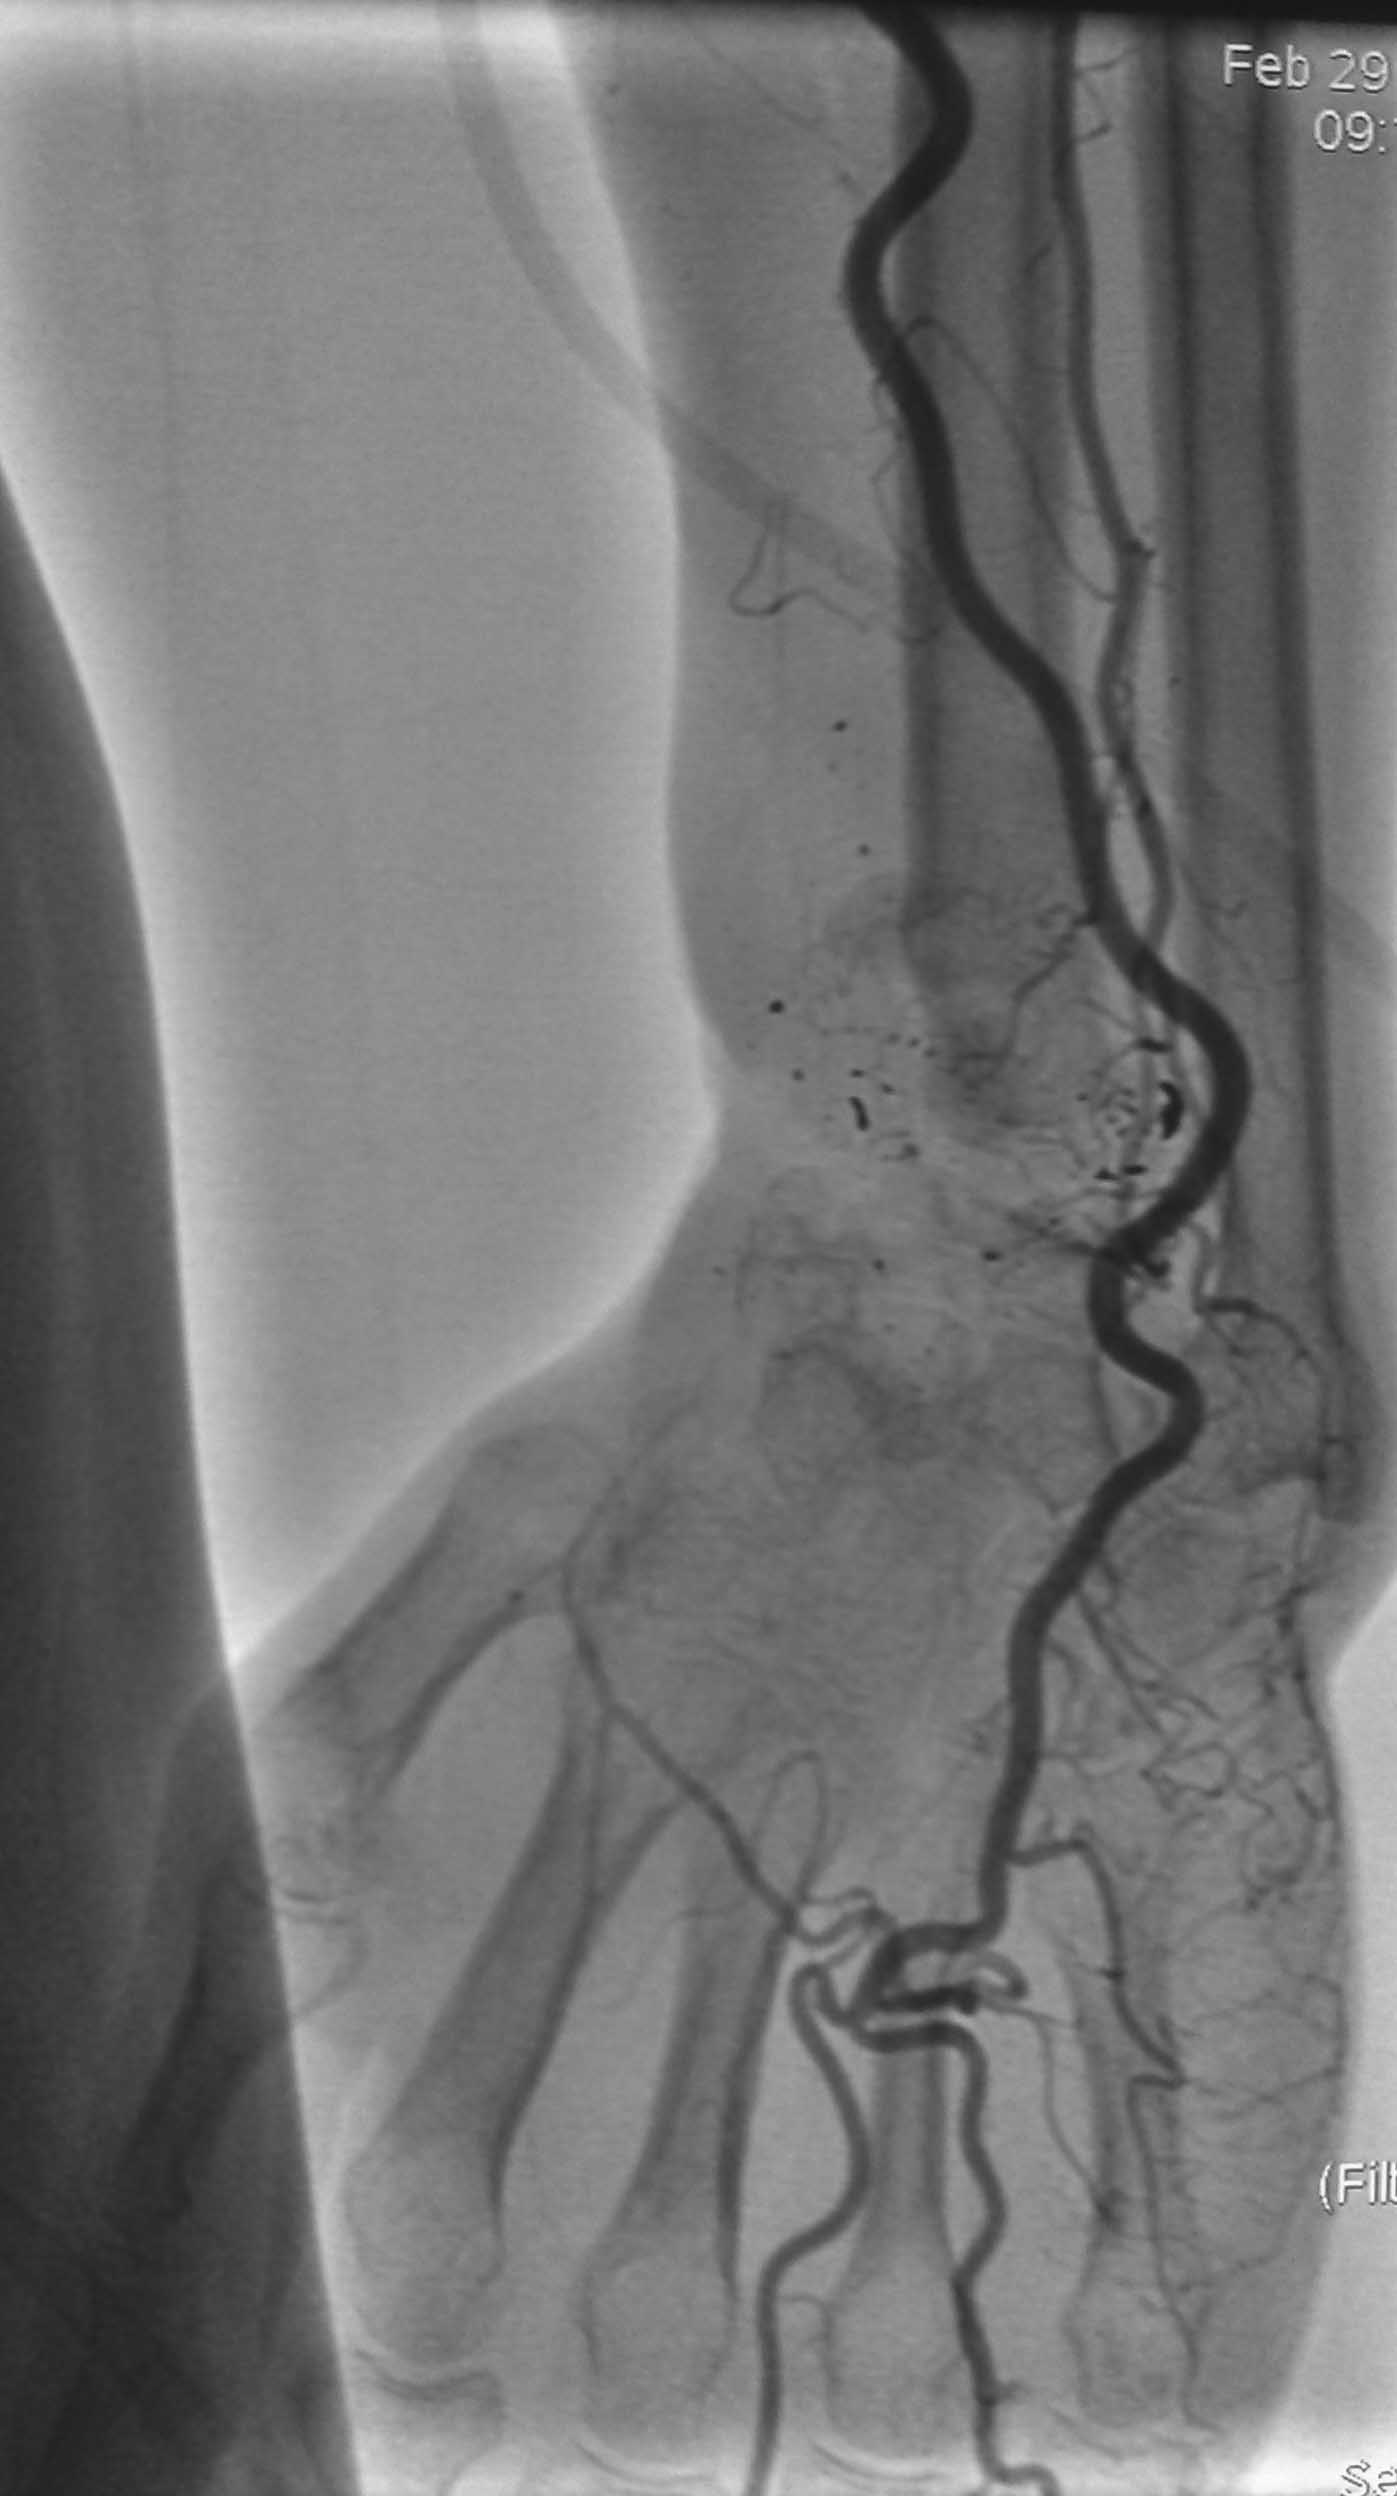

Изучали ли вы достаточно тщательно ангиограммы пораженного сегмента? Если да, то вы обратили внимание, что в артериальной фазе практически полностью отсутствует контрастирование лучевой артерии в зоне дефекта, тем самым вы имеете разорванную артериальную дугу и стабильный кровоток только в одном бассейне-локтевой артерии, тыльная межкостная не контрастировалась. Невзирая на это, вы предлагаете использовать пластику дефекта трансплантатом локтевой кости на сосудистом пучке (единственном, который объективно сохранился). Не боитесь ли вы возникновения проблем кровоснабжения кисти при выполнении данного вмешательства и как вы готовы бороться с этим (имею в виду оснащение, специалистов по микрохирургии и пр.)-это вопрос номер 2.